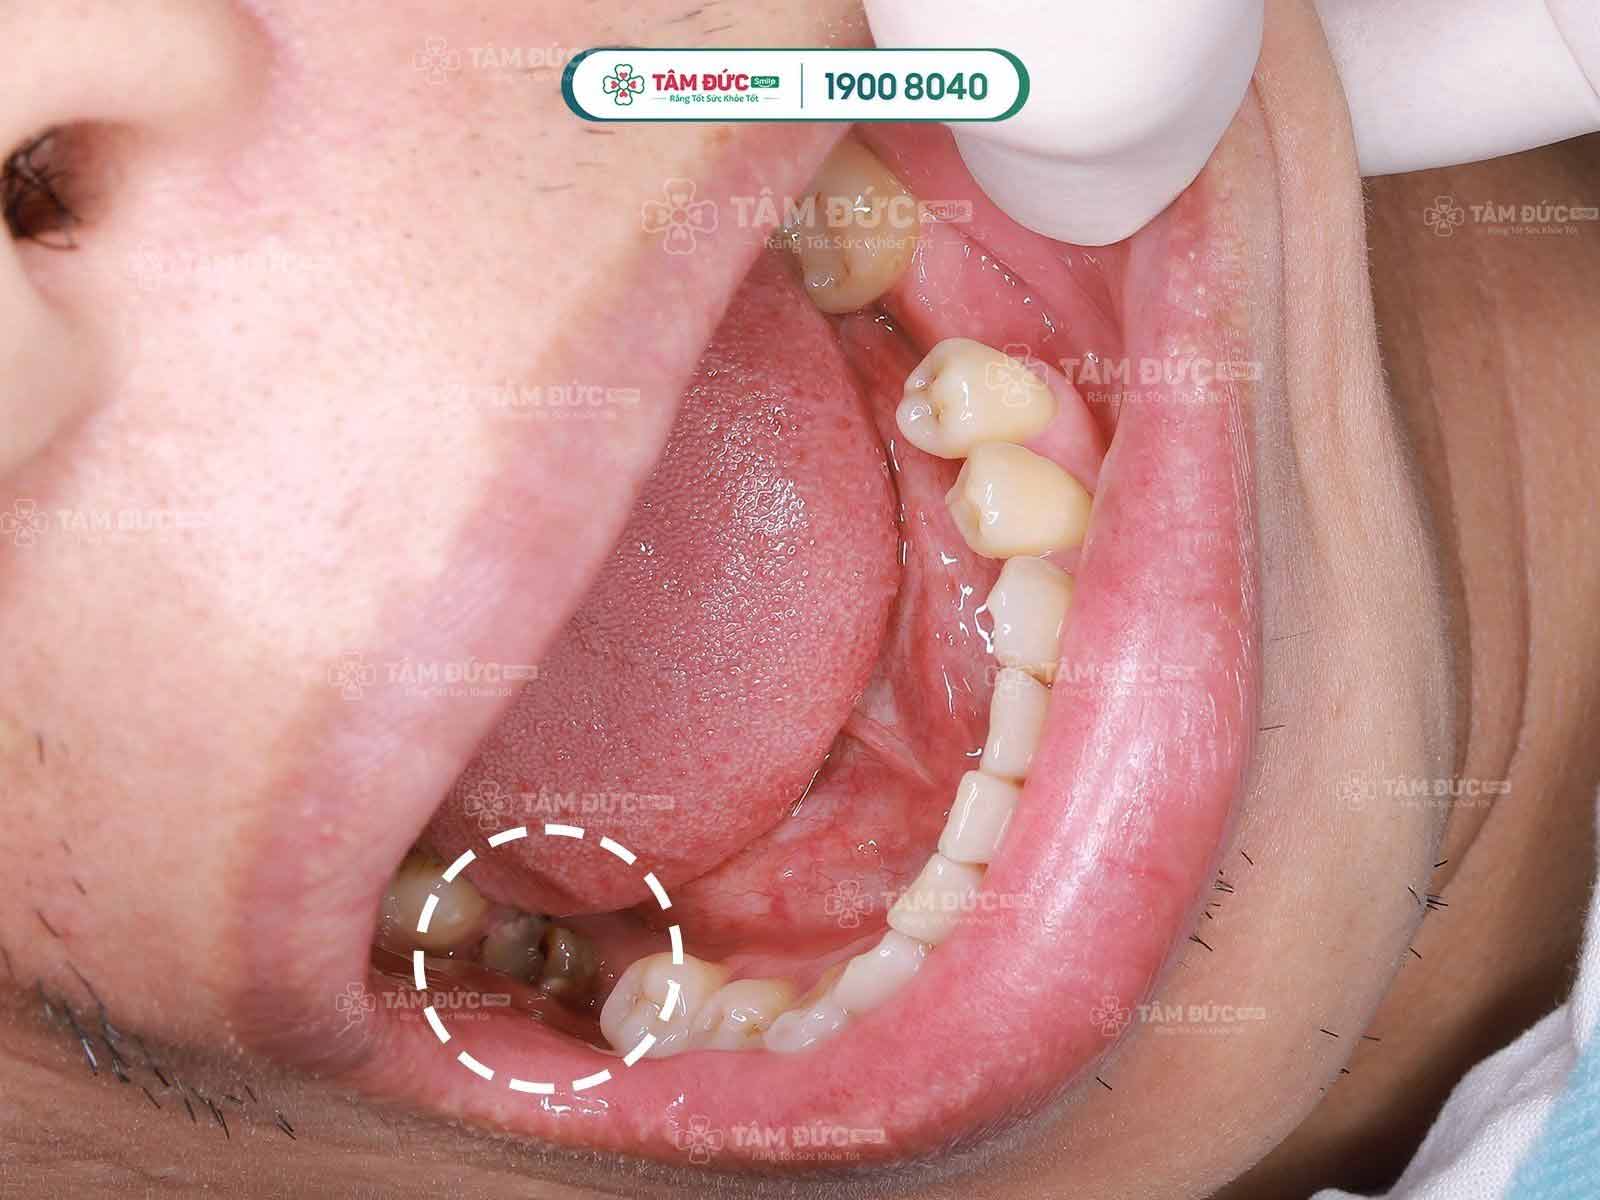

Sâu răng: lâu ngày sâu răng sẽ ăn vào tủy và gây các cơn đau dữ dội.

2.2. Nên lựa chọn cơ sở nha khoa uy tín để trám răng

Trám răng thẩm mỹ tuy là phương pháp nha khoa không quá phức tạp, tuy nhiên đòi hỏi tay nghề và chất liệu trám thật sự tốt để đảm bảo miếng trám vừa ổn định lâu dài và thẩm mỹ cao. Liệu trình trám răng thẩm mỹ được áp dụng cho những trường hợp: răng sâu, răng thưa, răng mẻ, viêm tủy…

Nếu không xử lý sạch những vùng răng sâu, viêm tủy; không xác định chính xác vị trí cần trám thì rất dễ xảy ra tình trạng:

- Bung miếng trám trong thời gian ngắn.

- Răng đau nhức sau khi trám.

- Răng trám không tự nhiên, màu răng không đều.